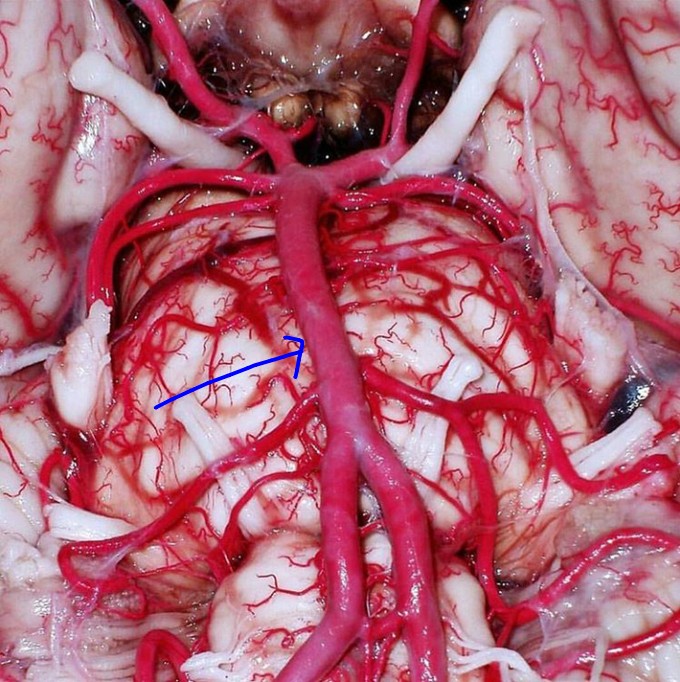

Troisier sign - an enlarged, hard, and often painless lymph node in left supraclavicular fossa (Virchow's node); Critical indicator of metastatic abdominal or thoracic cancer, most commonly gastric; Node acts as a final site for lymphatic metastasis